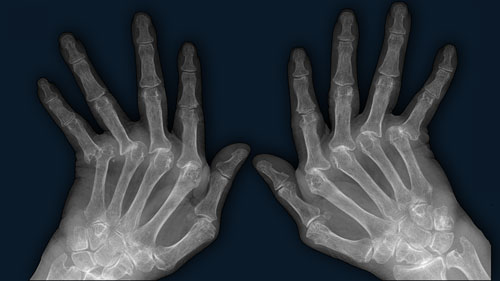

Arthritis